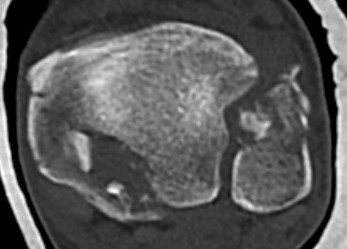

Mason and Malloy Classification

CT scan critical to classify and guide treatment / approach

| Type I | Type IIA | Type IIB | Type III |

|---|---|---|---|

| Avulsion of the PITFL |

Posterolateral fragment Volkmann fracture |

Posteromedial & posterolateral fragments Volkmann plus secondary fracture line |

Large coronal plane fragment Plafond fracture |